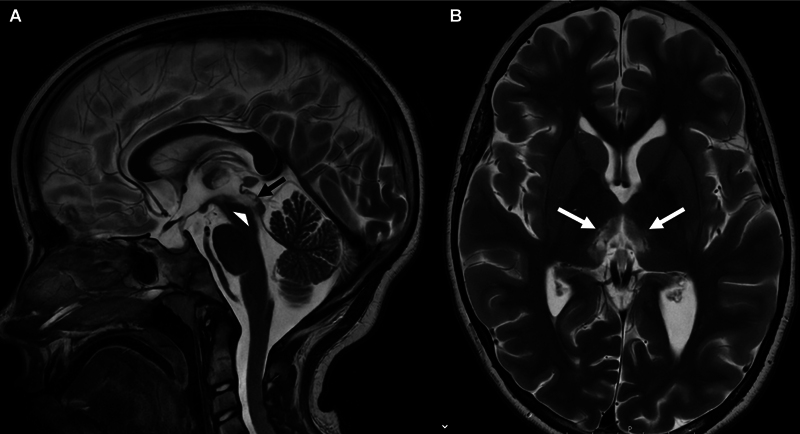

神经脊髓炎视谱障碍(NMOSD)是一种罕见的神经炎症性疾病,在白人人群中年发病率少于1例,发病年龄中位数为40岁。NMOSD通常表现为视神经炎和纵向广泛的横断面脊髓炎。各种脑干、小脑、间脑和半球症状也可能发生。早期诊断和治疗对于症状管理和预防复发和残疾至关重要。我们报告的情况下,青春期前的女孩,突出独特的临床和MRI特征和早期实质损害的风险。

Neuromyelitis optica spectrum disorder (NMOSD) is a rare neuroinflammatory disease with an annual incidence of less than 1 case in 1,000,000 in the White population and a median age of onset at 40 years. NMOSD usually presents with optic neuritis and longitudinally extensive transverse myelitis. Various brainstem, cerebellar, diencephalic, and hemispheric symptoms may also occur. Early diagnosis and treatment are crucial for symptom management and prevention of relapses and disability. We report the case of a prepubertal girl, highlighting unique clinical and magnetic resonance imaging features and the risk of early parenchymal damage.